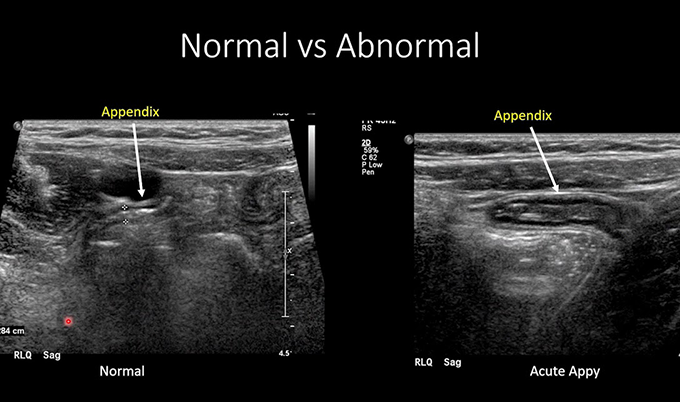

Ultrasound offers radiation-free imaging with sensitivity of 78-86% and specificity of 83-95% for appendicitis. It works particularly well in children, who have less abdominal fat allowing better sound wave penetration.

The 15-30 minute exam uses sound waves rather than radiation. A technologist applies gel and uses a handheld transducer with graded compression technique – gradually increasing pressure to displace gas-filled bowel loops and focus on the area of maximal tenderness.

On ultrasound, appendicitis shows characteristic features: a non-compressible tubular structure exceeding 6mm diameter, target sign or bull’s eye appearance on cross-section from wall thickening, increased blood flow on color Doppler, and free fluid around the appendix suggesting complication.

Ultrasound’s limitations are significant. Body habitus affects visualization – obesity makes it difficult to see deep structures. Bowel gas obscures the view. The exam is highly operator-dependent, meaning accuracy varies based on the technologist’s skill and experience. Most critically, ultrasound fails to visualize the appendix in 30-50% of cases. When the appendix isn’t seen, you can’t rule out appendicitis based on ultrasound alone.